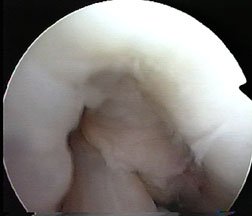

On the left ois a close-up photo of the notch area taken during arthroscopy. The cruciates are just entering the picture at the bottom.

Here again you see the notch between the two condyles, this time with the cruciate ligament labelled for you. You are looking from an angle, remember, and looking towards the medial femoral condyle on the right, while you can see on the left just an edge of the lateral femoral condyle.

The image is round. Why? Because it is being relayed to the camera via the round arthroscope.